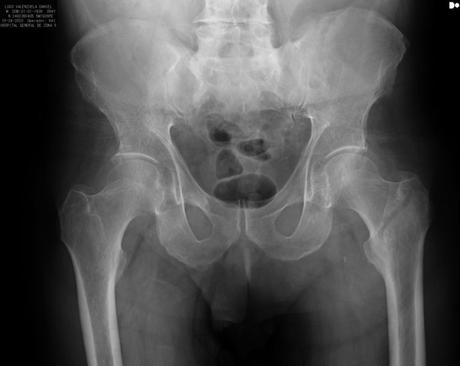

RADIOGRAFIA AP DE PELVIS DONDE SE OBSERVA PERDIDA DE CONTINUIDAD OSEA A NIVEL TRANSTROCANTERICO, TRAZO OBLICUO, NO COMPLETO, NO DESPLAZADO.

A. PACIENTE QUE PRESENTA FRACTURA INCOMPLETA A NIVEL TRANSTROCANTERICO FEMUR IZQUIERDO, NO AMERITA MANEJO QUIRURGICO. –